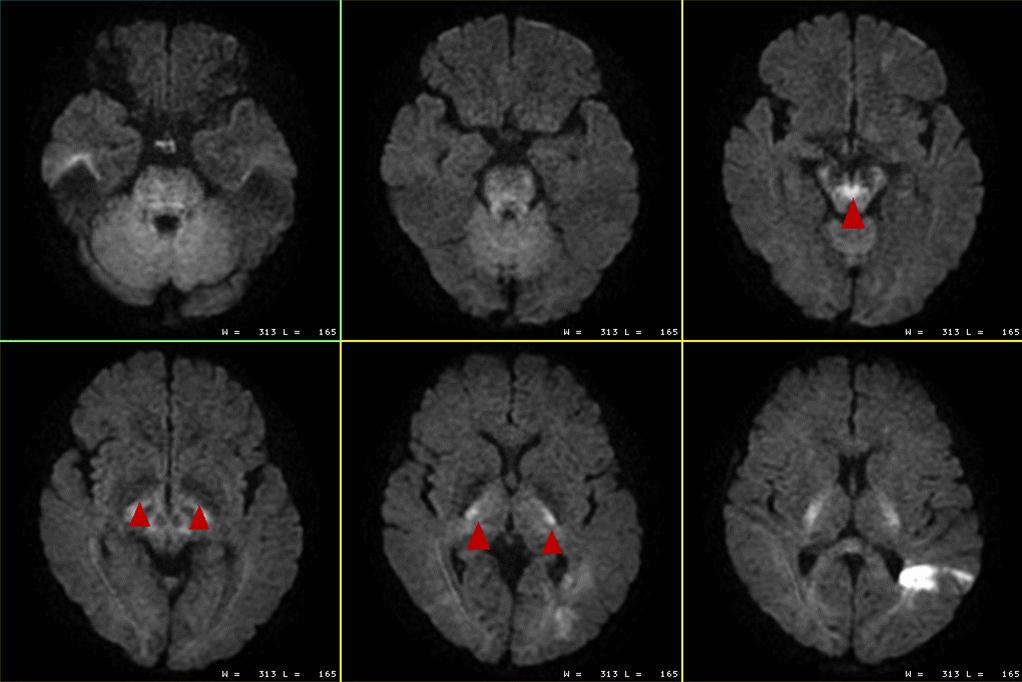

【DWI上这些均为正常影像表现,并无实际的临床意义】

成人脑在各向同性的DWI图像上很多结构会表现为高或低信号均为正常影像表现,并无实际的临床意义,如小脑上角的十字交叉、皮质脊髓束、扣带回、内囊后肢等处在DWI上均可表现为局灶性的高信号;由于生理性铁沉积在双侧苍白球处DWI可表现为低信号。虽然它们在DWI上信号表现为异常,但其ADC图上均表现为等信号。

新生儿颅脑也有类型的表现:

在DWI上额叶深部脑白质呈低信号,其相应区域的ADC值较高,均属于正常的影像改变。